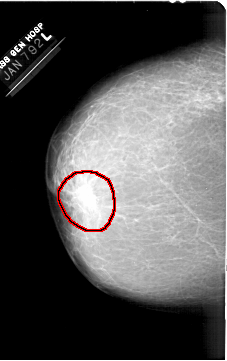

A_1380_1.LEFT_MLO

LESION_TYPE MASS SHAPE IRREGULAR MARGINS ILL_DEFINED

ASSESSMENT 4

SUBTLETY 5

PATHOLOGY BENIGN